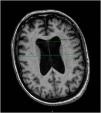

This report, details the case of a 61-year-old woman with a history of histrionic personality disorder and generalized anxiety disorder who developed severe pica, ingesting objects such as screws and jewelry. Initial psychiatric evaluations did not reveal a clear explanation for her behavior. However, further investigation identified significant cognitive decline, gait disturbances, and urinary incontinence—symptoms indicative of adult chronic hydrocephalus (ACH). A cranial CT scan confirmed ventricular dilation, leading to an ACH diagnosis. Pica disorder is often linked to frontal lobe dysfunction, common in ACH.

Este estudio describe el caso de una mujer de 61 años con antecedentes de trastorno de personalidad histriónica y trastorno de ansiedad generalizada, que desarrolló conductas severas de pica, mediante la ingesta de objetos como tornillos y joyas. Las evaluaciones psiquiátricas iniciales no revelaron una explicación coherente para su comportamiento. Sin embargo, una investigación más profunda, identificó la presencia de: deterioro cognitivo significativo, trastorno de la marcha e incontinencia urinaria, síntomas clásicos de hidrocefalia crónica del adulto (HCA). Una tomografía axial computarizada craneal confirmó la dilatación ventricular, lo que llevó al diagnóstico de HCA. El trastorno de pica a menudo se vincula con disfunción del lóbulo frontal, común en la HCA.